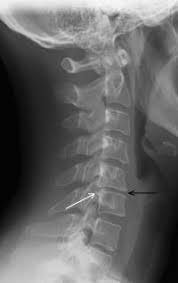

Other cervical disc degeneration at C5-C6 level Billable Code. Cervical degenerative disc disease is a common cause of neck pain and radiating arm pain. Icd-10 has specific codes for lumbosacral disc displacement and degeneration with radiculopathy that was not present in ICD-9.

ICD-10 requires to specify the presence of radiculopathy with disc displacement and degeneration. The ICD code M50 is used to code Spinal disease.